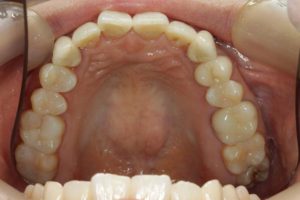

どのように変わったか、下の写真をご覧ください。

銀歯が多かったのですべて昔の銀歯の下もちりょうしながらセラミックにかえることができてとても満足しています。やっぱり白い歯よいですね。

治療お疲れ様でした。たくさん銀歯が入っていたのですが、最後には真っ白になりましたね。銀歯をやり直す材料にはセラミックとプラスティックがあるのですが、基本的にできるだけプラスティックで治すようにしています。この患者さんも、可能な限りプラスティックで治し、どうしても無理なところだけセラミックにしました。そのため歯を削る量が少ないことに加え、費用もかなり抑えることができます。たくさん治しましたが、全部セラミックで治さなければならないとなっていたら、もっともっと時間も費用もかかっていたかもしれません。当院では、初診時に治療方針や期間や費用などを1時間ほどかけて詳しく説明していますので、患者さんには治療内容について十分納得していただいていると考えています。「親身になって治療してくれる」とおっしゃっていただいたことは、そういったところを評価して頂いたのではいかと思っております。